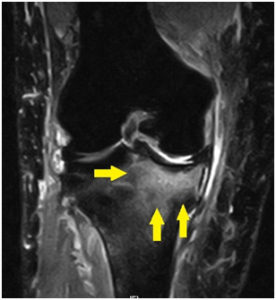

骨の中がむくんだり、血が溜まったり、炎症をおこすことを骨挫傷といいます。

骨といえばレントゲンというイメージが強いですが、骨挫傷はレントゲンで分かりません。

MRIで骨をみるとわかります。